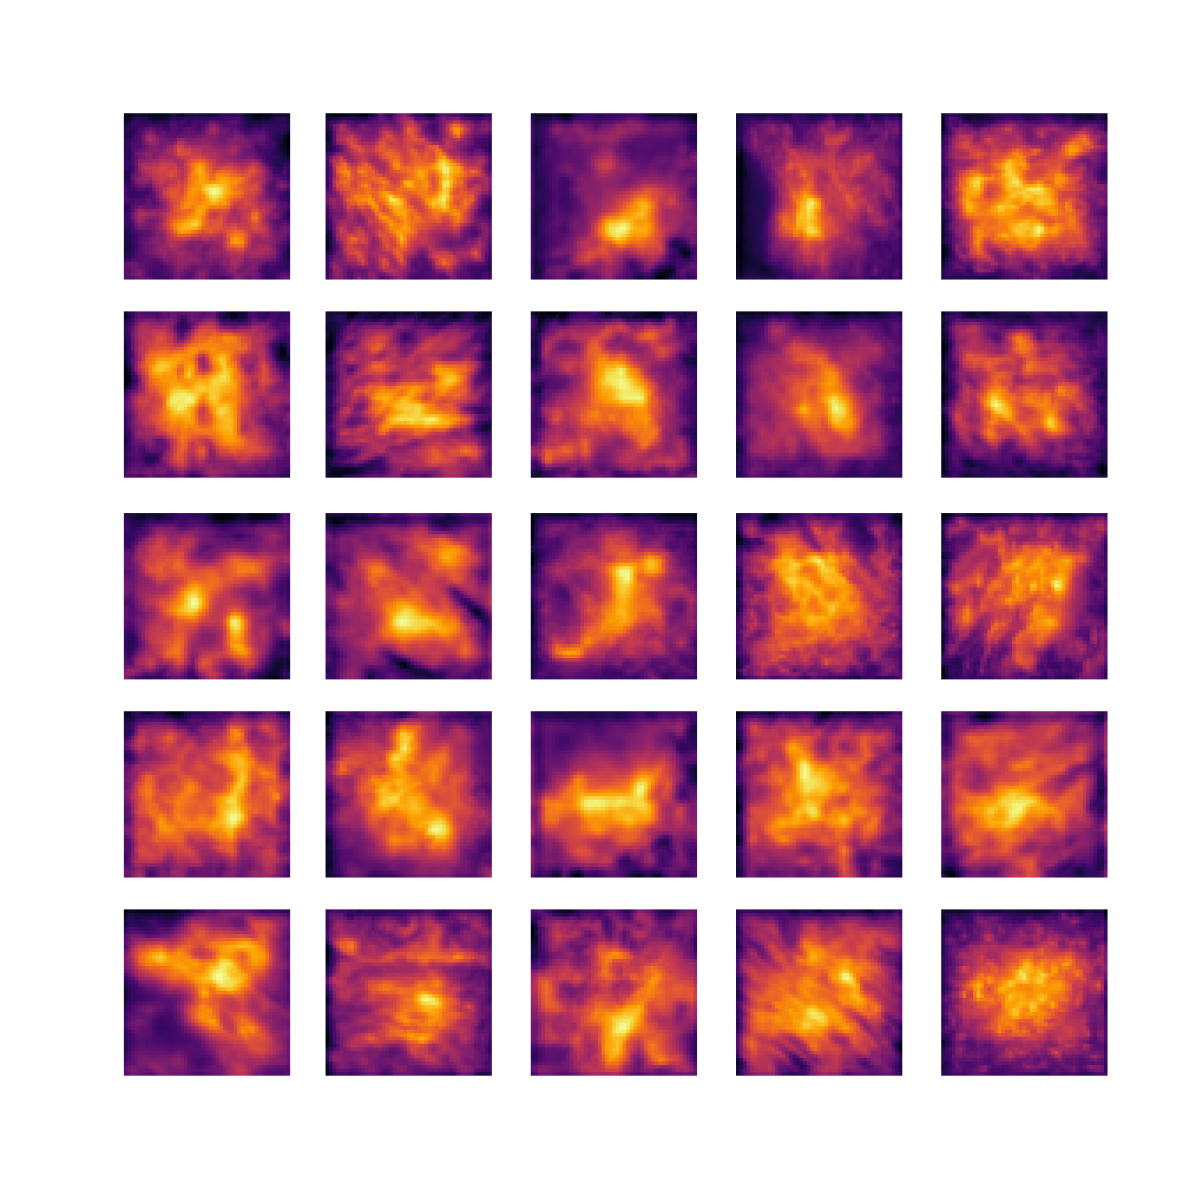

We also analyse the activation maps for each model using GradCAM as described in section S3. This offers more insight into the areas of the image which are contributing most heavily to the models’ representations. In Figure 4(b) we present some representative examples, however, a larger selection which was chosen at random is presented in Figures S10 to S25. The larger selection makes it easier to see the emergent patterns, including that privileged Siamese models tend to mainly identify features which are strongly present in both inputs, while unprivileged Siamese models tend to learn more diffuse features that are not specific to one cell phenotype or image region. TriDeNT ♆ incorporates both sets of features, learning both features specific to the privileged data and more the general features associated with unprivileged Siamese networks.

We can see in Figure 4(b) panel A that for ERG, the privileged Siamese model focuses almost exclusively on any nuclei which could be endothelial cells. As there are very few endothelial cells in the dataset, it could be an effective strategy to identify anything that could potentially be an endothelial cell to minimise the difference between the representations of the H&E model and the IF mask model. In the corresponding unprivileged Siamese image, we see that the model identifies some of these nuclei, albeit less strongly, but also focuses heavily on the other tissue and even the background, while strongly fixating on two spots of debris in the center of the image. This model has less ‘incentive’ to learn the weak features related to endothelial cells as these occur rarely and are not easy to detect, while more generic strong features such as the presence of connective tissue and the prevalence of background are more common and predictable from augmented images. We see that TriDeNT ♆ combines these two feature sets, strongly identifying nuclei while also identifying the connective tissue.

In panel C we see a similar pattern, with the privileged Siamese model fixating solely on the nuclei, while the TriDeNT ♆ model takes a more balanced approach. The unprivileged Siamese model appears to focus on a single cluster of nuclei while neglecting others, and similarly identifies an area of fibroblasts with its distinctive pattern but does not others.

In contrast to panels A and C which represent models with poor privileged Siamese results, panels B and D represent models whose privileged Siamese results were comparable to both TriDeNT ♆ and even the supervised baseline. It is therefore interesting to note that there are far more similarities between the privileged Siamese and TriDeNT ♆ models in both cases. Particularly in panel B, TriDeNT ♆ and the privileged Siamese model return virtually identical heatmaps, with both strongly identifying epithelial nuclei and neglecting the same areas of connective tissue. The unprivileged model in this case appears to focus solely on the centre of the image, giving a significantly different heatmap to the other panels.

Panel D again shows the previous pattern, with the privileged Siamese model identifying the features strongly present in the privileged data – fibroblasts – while neglecting the nuclei present. TriDeNT ♆ also strongly identifies the connective tissue, but, unlike the privileged Siamese model, does not completely neglect the nuclei. The unprivileged Siamese model primarily identifies background, and does not appear to identify the nuclei in this example.